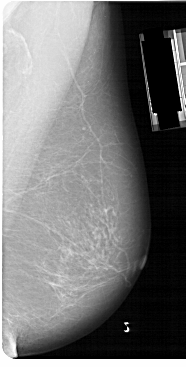

A_1149_1.LEFT_MLO

LEFT_MLO LINES 5491 PIXELS_PER_LINE 3031 BITS_PER_PIXEL 12 RESOLUTION 43.5 OVERLAY